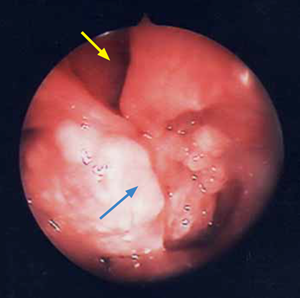

Un bilan d’extension local est réalisé à l’aide d’un examen tomodensitométrique des cavités nasales (Photos 23 et 4).

Un envahissement des cavités nasales droite et gauche par une masse à prise de contraste hétérogène est observé. Le bulbe olfactif et le lobe frontal droit sont envahis. Des images lytiques des

cornets nasaux, volutes éthmoïdales, septum, vomer, lame criblée et os frontal sont visualisées.

Photo 3 Examen tomodensitométrique. Le reformatage dorsal permet de visualiser l’extension de la tumeur (flèches).

Photo 4 Examen tomodensitométrique. Noter l’effondrement de la lame criblée de l’ethmoïde par la tumeur nasale (flèches).